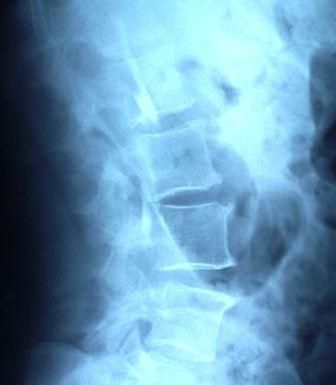

A 46-year-old man with a history of HIV infection presented with left flank pain. A lateral x-ray film of his lumbar spine shows erosion of the anterior vertebral end plates both above and below the involved disc space, consistent with discitis.